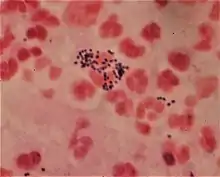

Micrograph of a gram-positive coccus and a gram-negative rod.

A Gram stain of mixed Staphylococcus aureus (S. aureus ATCC 25923, gram-positive cocci, in purple) and Escherichia coli (E. coli ATCC 11775, gram-negative bacilli, in red), the most common Gram stain reference bacteria